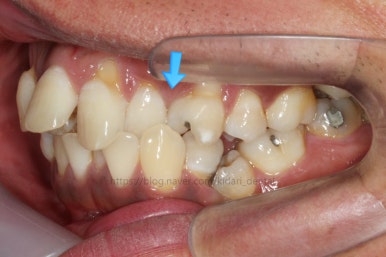

화살표를 보면 작은 어금니 하나가 아래로 꺼져있는데, 이 녀석 때문에 애를 먹었네요. 훨씬 치료가 빨리 끝날 수 있었는데 이 치아가 워낙 잘 안움직이는 바람에 2년 개월정도로 치료기간이 많이 걸린 편이었어요.

치료 8개월째의 모습입니다.

이제 얼핏 보면 매우 가지런해졌어요. 이 뽑은 자리도 많이 남지 않았고 왼쪽 위 송곳니가 없지만 그리 표시도 많이 나지 않네요.

대신 위쪽 아래 작은 어금니가 애를 먹이고 있어요. 낚시줄처럼 부여매고 끌어올리는게 보이실거에요.

뼈에 단단히 붙어 안움직이는 경우를 "유착치아"라고 표현하는데, 유착치아라면 해당 치아를 움직이는 것을 포기했어야 했어요.

그래도 조금씩이라도 움직이고 있어서 계속 시도했습니다.